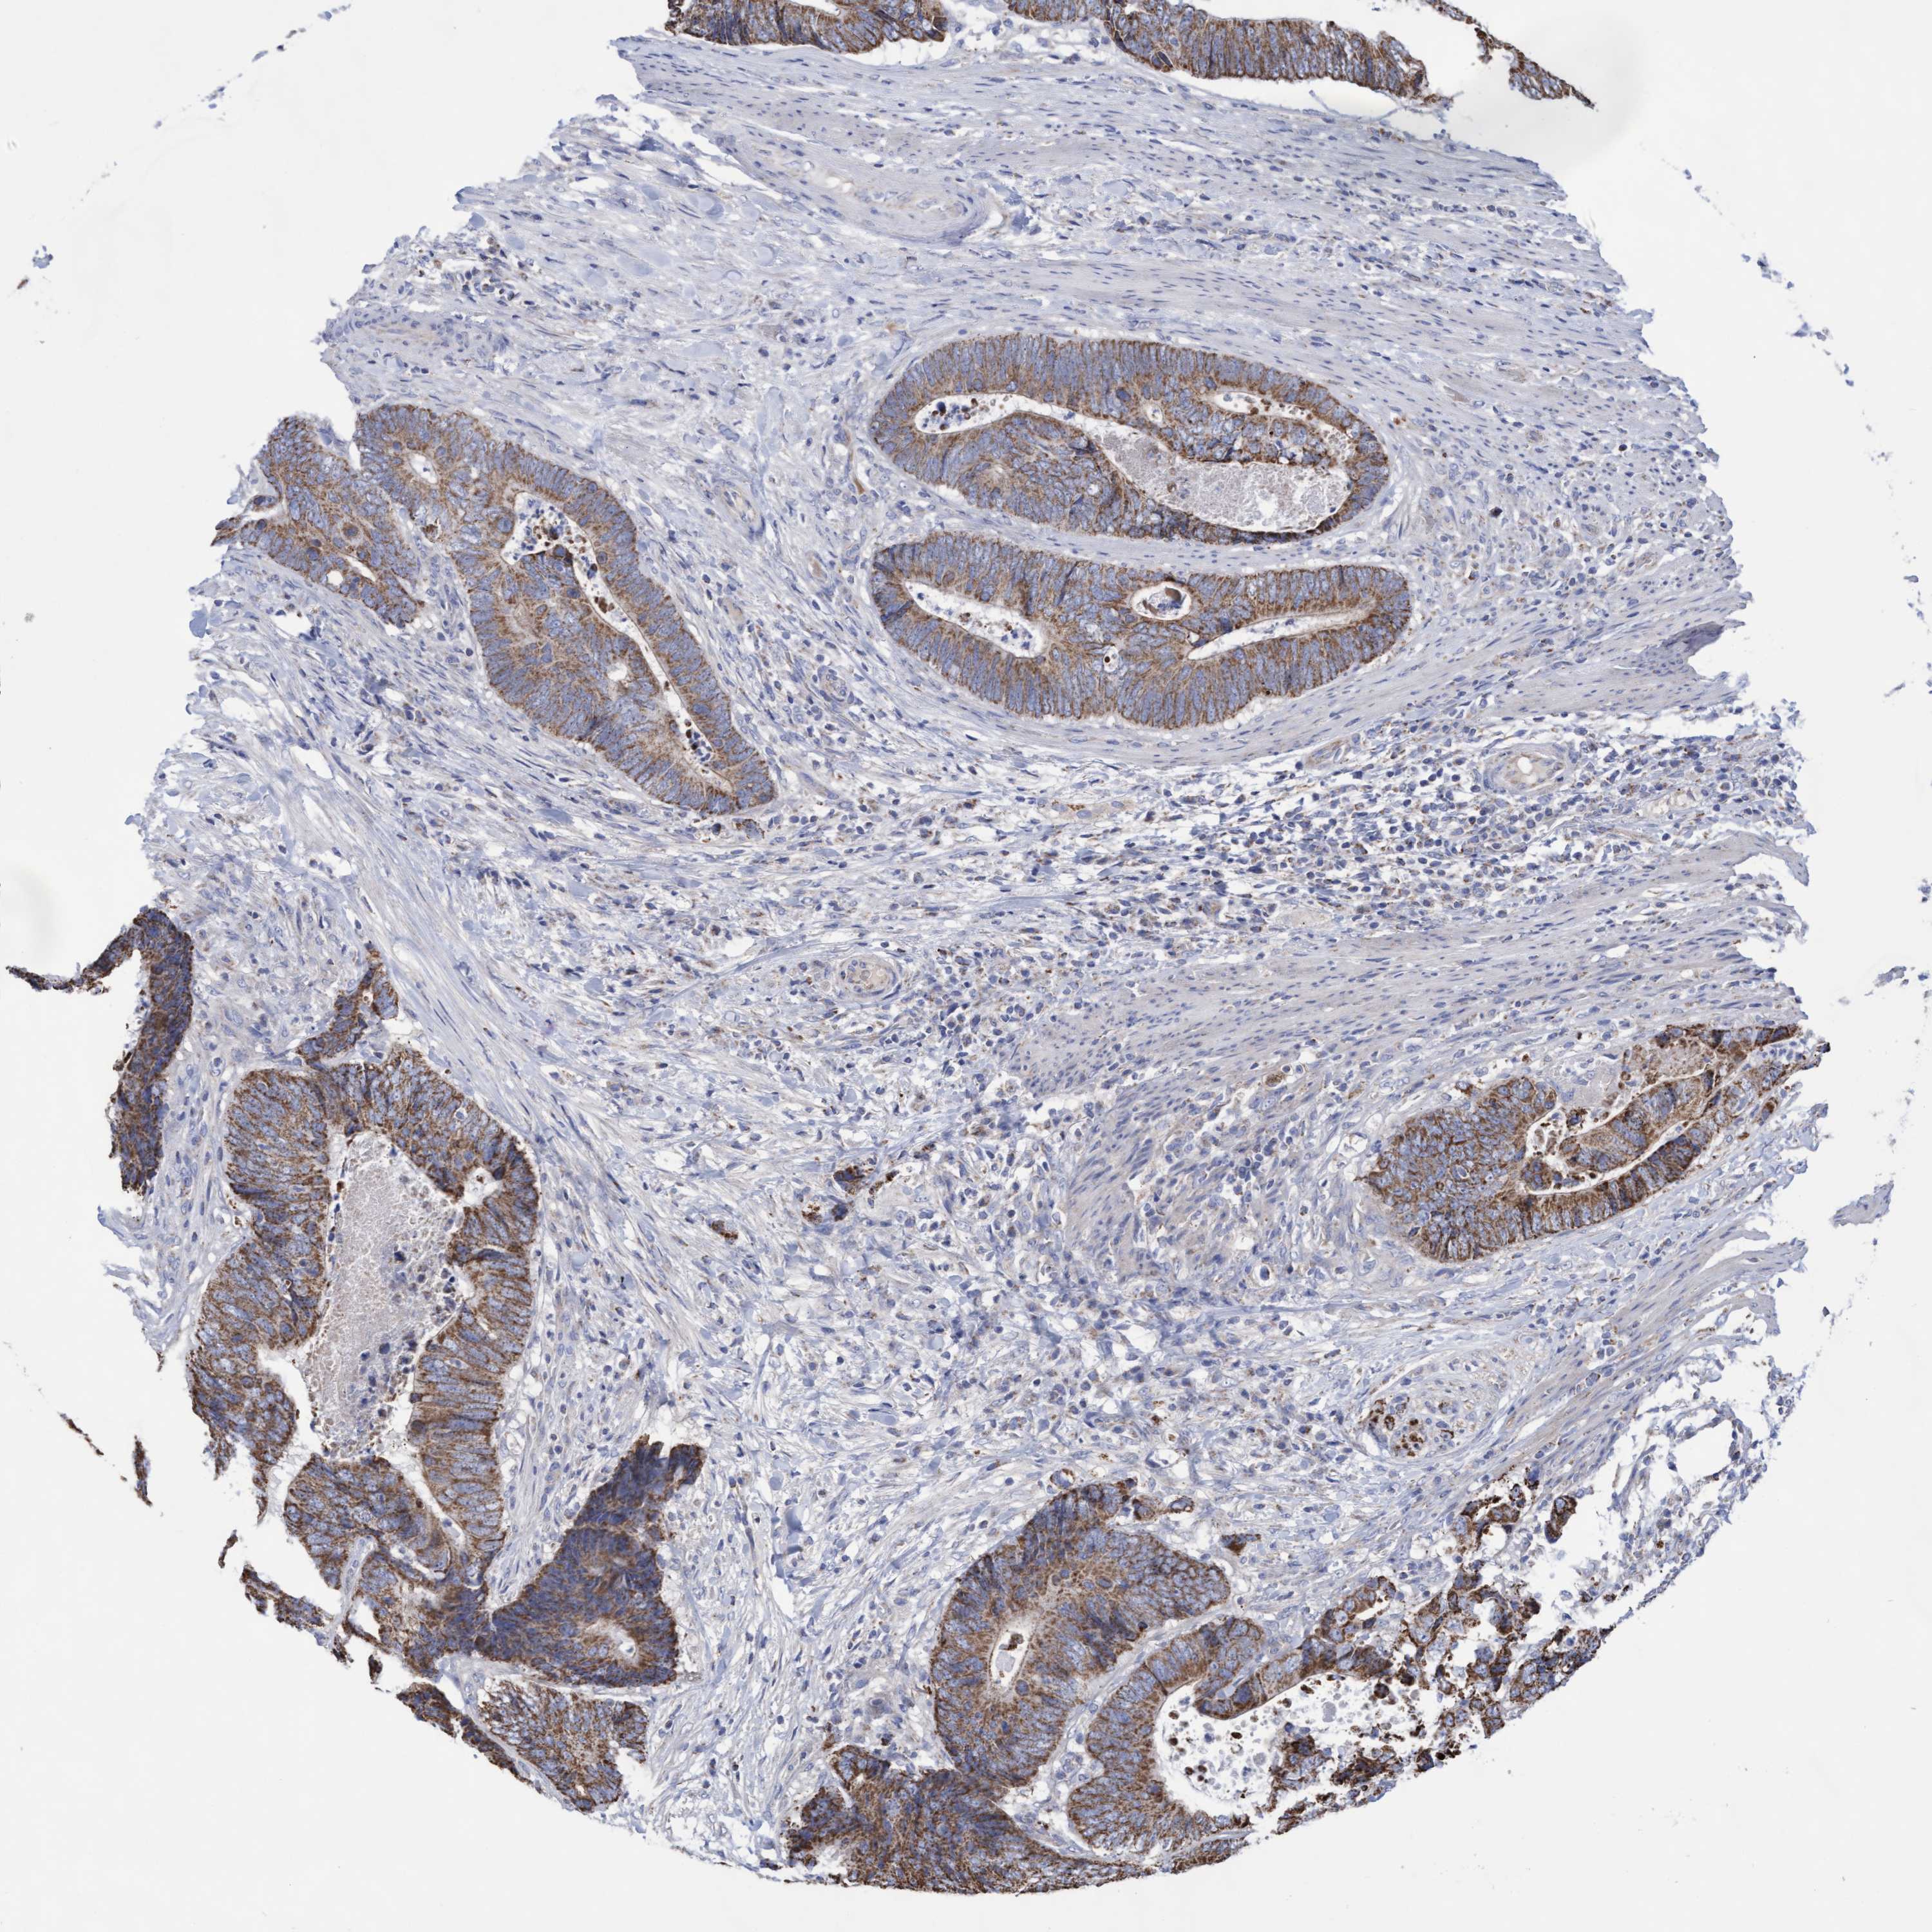

CANCER COLORECTAL CANCER Show tissue menu

Colorectal cancer

Human cancer

Colon adenocarcinoma